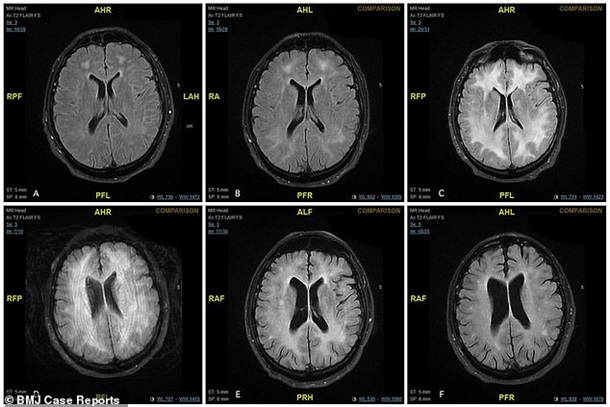

Лікарі запідозрили інфекцію, але приписане лікування не допомагало. Тоді фахівці зробили чоловікові МРТ і діагностували прогресивну лейкоенцефалопатію. Вона була викликана тривалим прийомом кокаїну. Через кілька днів пацієнт впав у кому через пошкодження мозку.

Лікарі продовжили лікування чоловіка, і весь час робили знімки мозку пацієнта. Повідомляється, що білі плями на фото - це мертві клітини мозку, які змогли відновитися. На корі головного мозку пацієнта залишилися шрами навіть через рік.